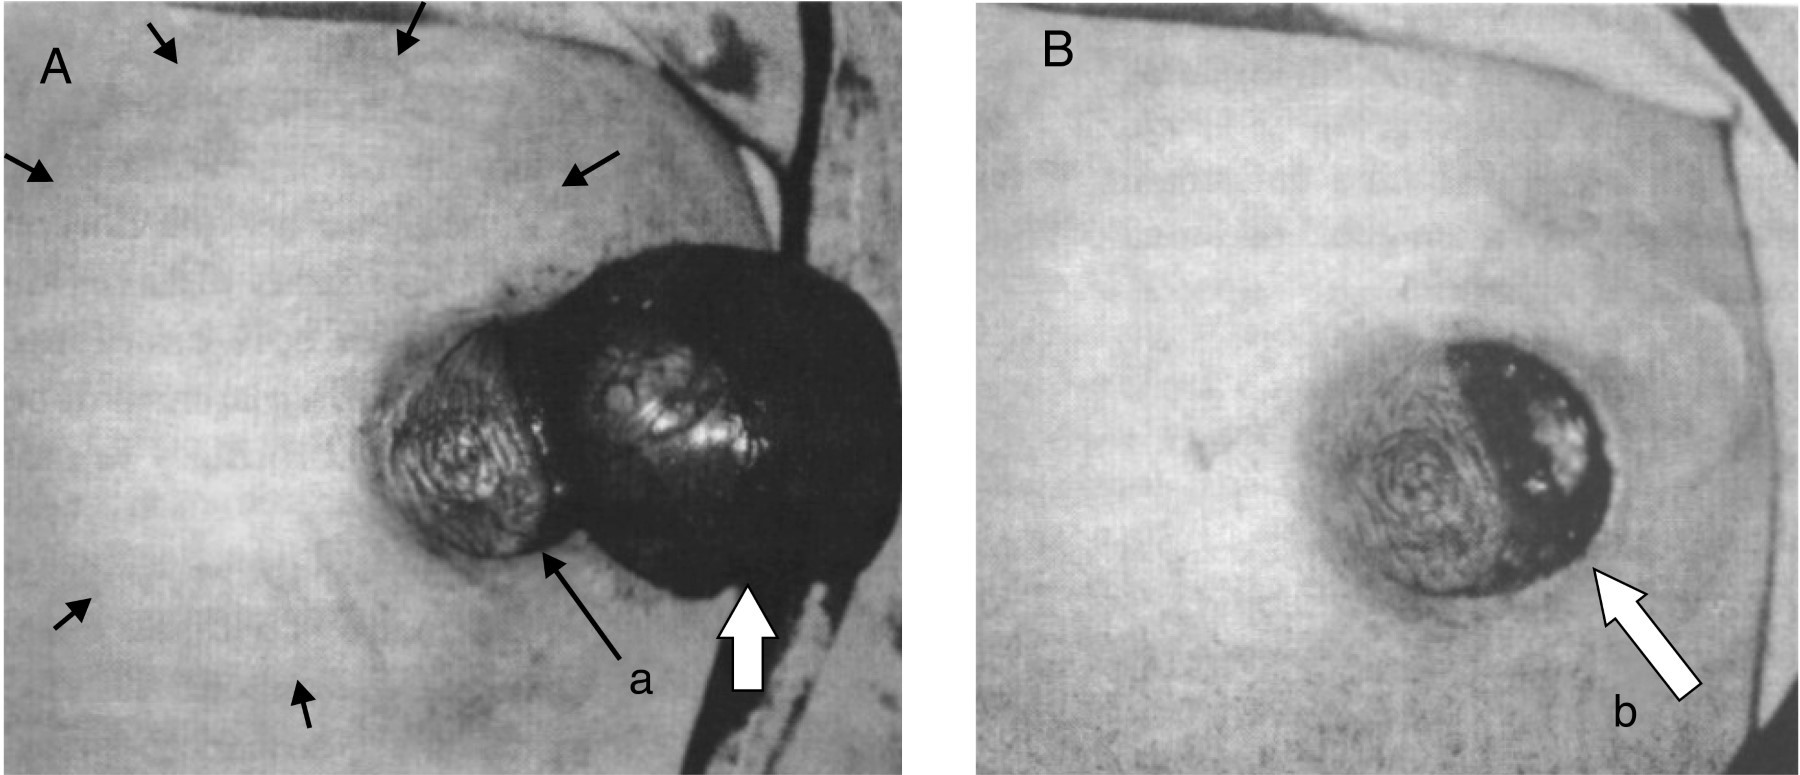

La glándula mamaria es una glándula sudorípara modificada y especializada. Durante la cuarta a sexta semana de vida fetal se desarrollan las yemas mamarias. Estas aparecen como un crecimiento sólido en la epidermis (ectodermo) hacia el mesénquima subyacente (Figura 1- A, a).

Las líneas mamarias se observan por primera vez en la pared ventral del feto durante la sexta semana de gestación, extendiéndose bilateralmente desde el tercio lateral de la clavícula hasta la sínfisis del pubis. Las líneas mamarias presentan regresión excepto en el área torácica bajo la influencia de diversas hormonas que se diferenciará en tejido mamario que dará origen a la glándula mamaria (Figura 1A, b). En el quinto mes de gestación ya se observa el pezón, la aréola y una ramificación de 15 a 25 conductos, junto con tejido conectivo de sostén. Al llegar a la semana 32 de gestación la glándula crece por influencia de las hormonas maternas. En la mayoría de los neonatos a término es palpable el tejido mamario de aproximadamente 8 mm. El crecimiento de la glándula continúa después del nacimiento, alcanzando en promedio los 14 mm de diámetro. Subsecuentemente cada yema primaria da origen a varias yemas secundarias que se diferencian en conductos galactóforos (lactíferos) y sus ramas (Figura 1B; B-1 a la B-4). La canalización de estas yemas para formar conductos es inducida por hormonas sexuales de la placenta que alcanzan la circulación fetal. Esto continúa hasta término con la formación de 15 a 20 conductos galactóforos (Figura 1B-4). Mientras tanto el tejido conjuntivo fibroso y la grasa de la glándula mamaria se desarrollan del mesénquima circundante. Al final del periodo fetal, la epidermis se deprime en el sitio de origen de las glándulas mamarias, que en conjunto con la proliferación del tejido conectivo circundante a la aréola y el área circular de piel que rodea al pezón, dan origen a la fovea mamaria (Figura 1B-3). En los recién nacidos se pueden observar los pezones recién formados y deprimidos. Las células mesenquimatosas vecinas se diferencian y forman las fibras de músculo liso del pezón y de la aréola. Al nacer sólo están formados los principales conductos galactóforos y la glándula mamaria permanece latente hasta la pubertad. Las glándulas mamarias son idénticas, se desarrollan en forma similar y tienen la misma estructura en ambos sexos.